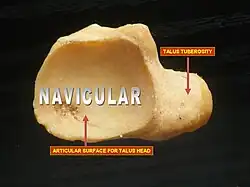

Navicular

The navicular, deriving its name from its boat–like shape, is a small but critical bone. It connects the ankle with the bones of the foot. It articulates with five tarsal bones (talus, cuboid, and three cuneiform bones) forming slightly mobile syndesmotic (fibrous) joints and has a significant function in maintaining the arch and the dynamic biomechanics of walking. The middle third of the bone lacks blood vessel penetration and it bears the majority of the load applied to the tarsal bones during weight bearing. Its vascular and biomechanical properties make it susceptible to injury. This may partly explain a higher risk of stress fractures and osteonecrosis in this location. Athletes who run, cut and pivot are particularly susceptible to injuries in this area. It is known as the keystone of the foot[10] and injuries to it can be "exasperating."[11]